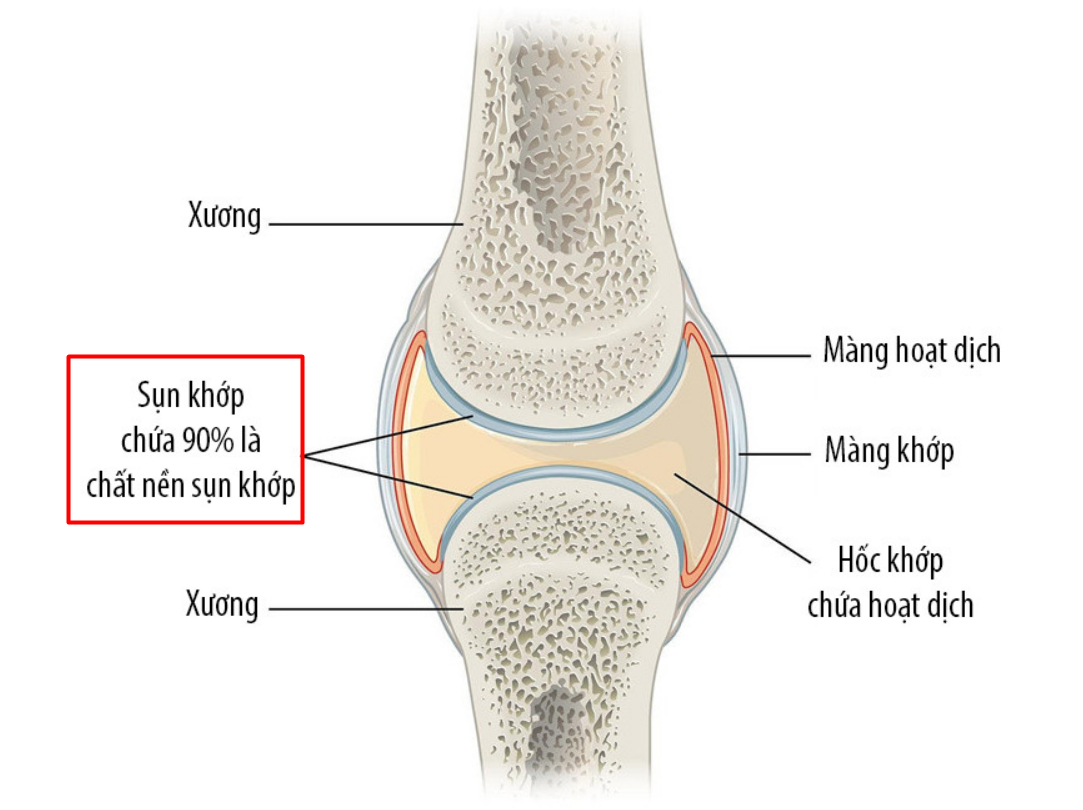

|

| Hình ảnh cấu trúc của sụn khớp |

Chất nền sụn khớp (ECM) là cấu trúc bên ngoài các tế bào sụn, chiếm trên 90% thành phần sụn khớp.Chất nền sụn khớp là thành phần chính tạo sự dẻo dai, bền bỉ, khả năng chịu các lực nặng của khớp khi vận động, thông qua mạng lưới liên kết giữa các glycoaminoglycans – collagen - acid hyaluronic. Vì thế, đây là thành phần vô cùng quan trọng và có vai trò quyết định đối với sự phục hồi được tổn thương sụn khớp.